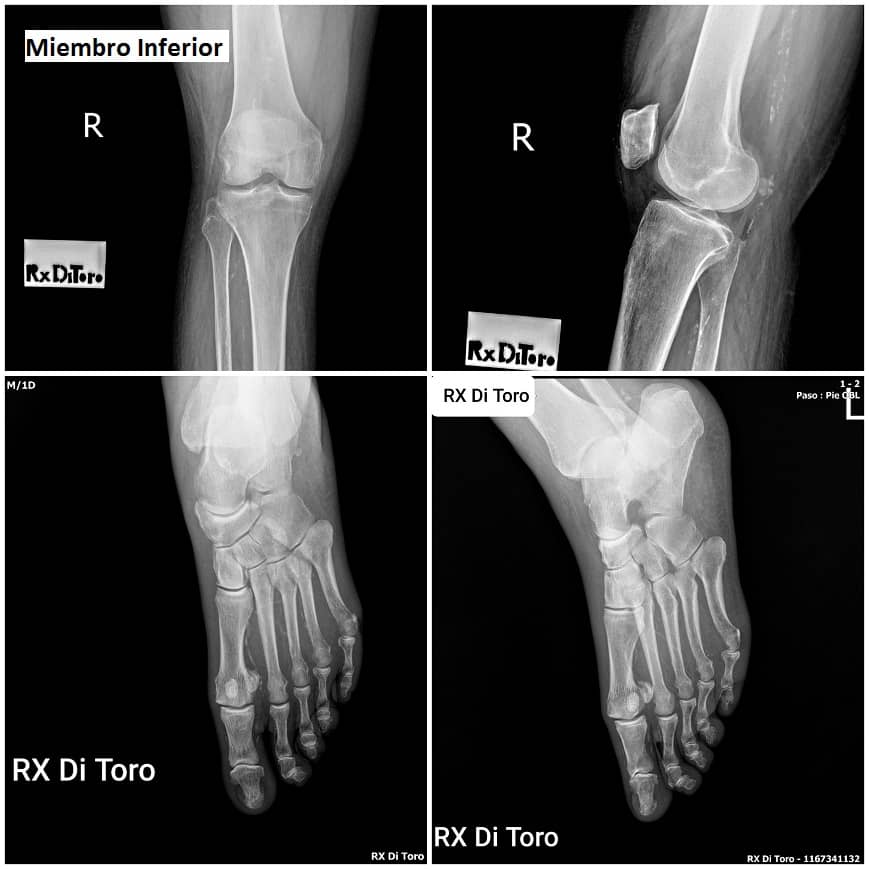

Utilizamos sensores Flat Panel, que nos permiten acortar al Máximo el tiempo de exposición (Dosis de Radiación) y obtener la adquisición inmediata de las imágenes.